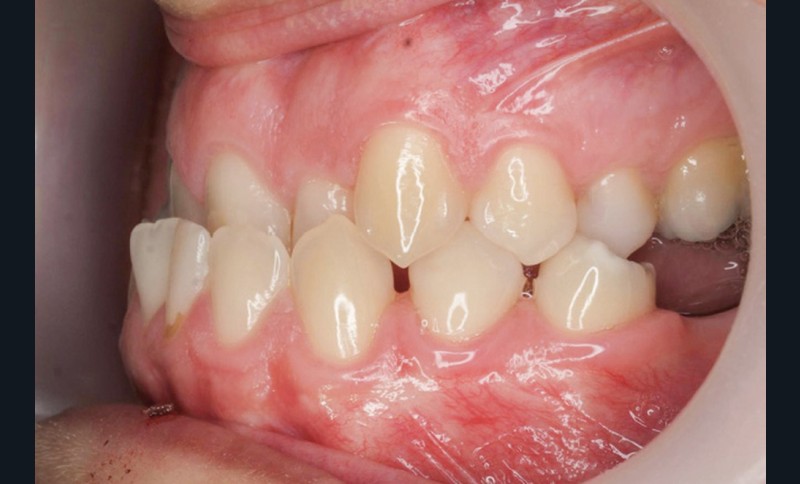

Diagnostic (fig. 1a-g)

La patiente présente une classe III squelettique dans un contexte hyperdivergent associée à une endoalvéolie maxillaire, un articulé inversé antérieur, une rétroversion incisive maxillaire, des rapports de classe I canine bilatérale, une absence de 16 et 36.

Au niveau esthétique, le profil est rectiligne. La lèvre supérieure est plus effacée, en retrait par rapport à la lèvre inférieure. De face et de profil, la mandibule paraît massive et le maxillaire effacé : le manque de soutien de la lèvre supérieure contribue à cette impression.

Le sourire est étroit, dégradé par les malpositions dentaires.

Au niveau fonctionnel, il existe un pro-glissement mandibulaire et un articulé inversé antérieur. Le profil téléradiographique montre en occlusion des rapports labiaux et un profil de classe III plus marqué que sur photographies.